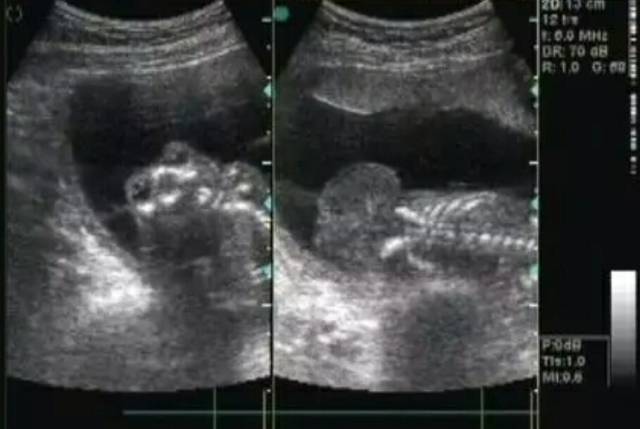

胎儿神经管发育畸形

胎儿神经系统畸形

各种胎儿神经管畸形的超声与 mri 特征

受到遗传或环境等因素影响,导致神经管闭合不全,形成无脑畸形,脊柱裂